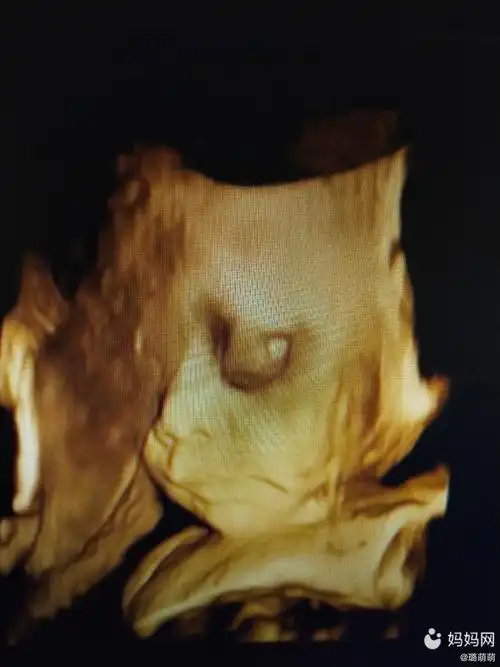

孕妇做四维彩超时为啥宝宝总是捂着脸3个原因很常见

二次四维顺利通过,就是宝贝每次不配合不给看脸,每次都是侧脸.

宝贝的四维彩超不知道生下来跟四维一样不一样小脸蛋太_妈妈网孕育